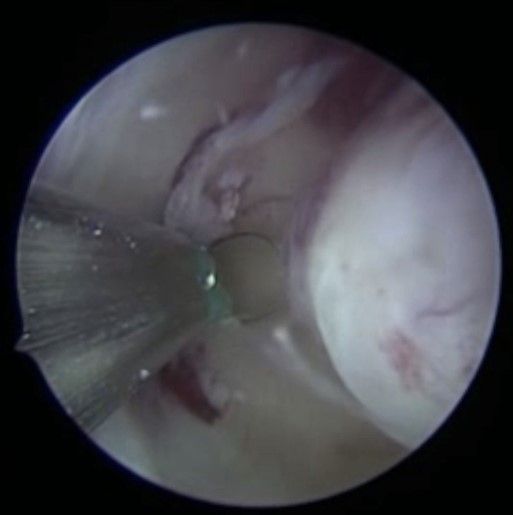

Bei der Gebärmutterspiegelung wird die Gebärmutterhöhle mit Kochsalzlösung aufgedehnt. Eine Kamera mit integrierter Elektroschlinge wird in die Gebärmutter eingeführt. Die vorhandenen Myome können nun schrittweise unter Sicht abgetragen werden. Mittels modernsten Ultraschalluntersuchungen werden die Myome während der Operation noch einmal genau dargestellt. Bei sehr großen Befunden können zwei Operation zur kompletten Myomentfernung notwendig sein.

3 Monate nach einer solchen Operation kann mit der Kinderplanung begonnen werden. Blutungsstörungen werden in aller Regel bereits zur nächsten Menstruation gebessert sein. Der Eingriff per Gebärmutterspiegelung wird meistens in Vollnarkose und ambulant durchgeführt. Bei kleinen Myomen kann der Eingriff, dank neuester, kleinen Instrumente, auch in lokaler Betäubung ohne Narkose durchgeführt werden.